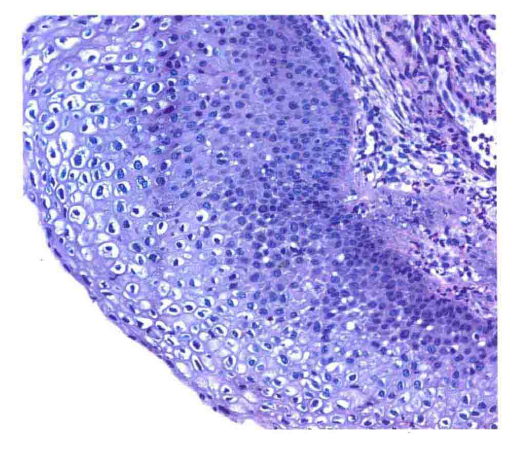

示不典型挖空细胞,核大,深染,可见核皱褶